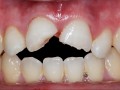

TEMAT NUMERU: Urazy i złamania – wyzwania stomatologii

Magazyn Stomatologiczny 11/2025